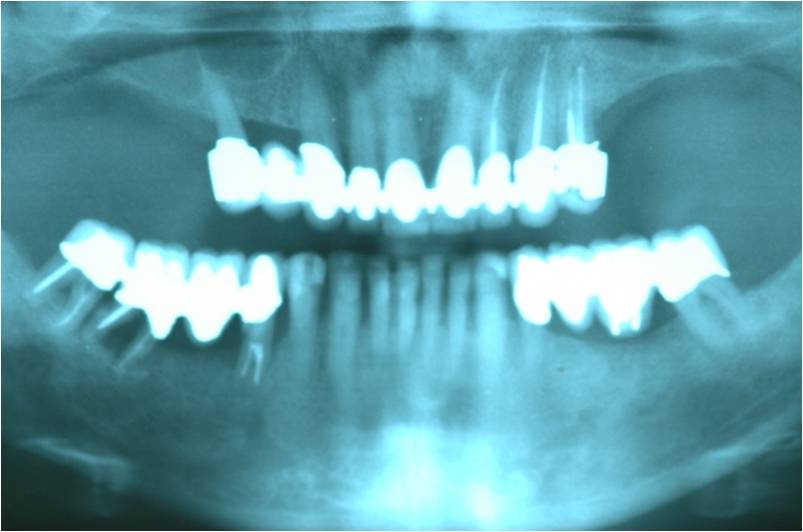

מקרה המתאר חוסר שיניים מוחלט בלסת עליונה.